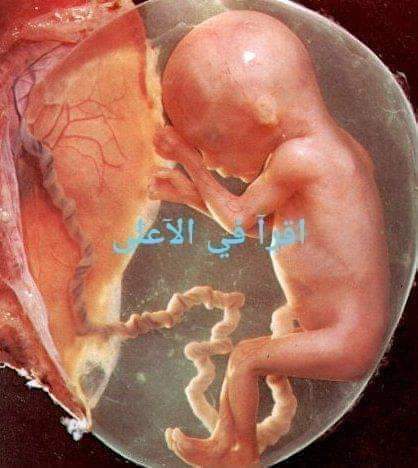

Фотография Плода В Животе

Фотография Плода В Животе 113 фотографий